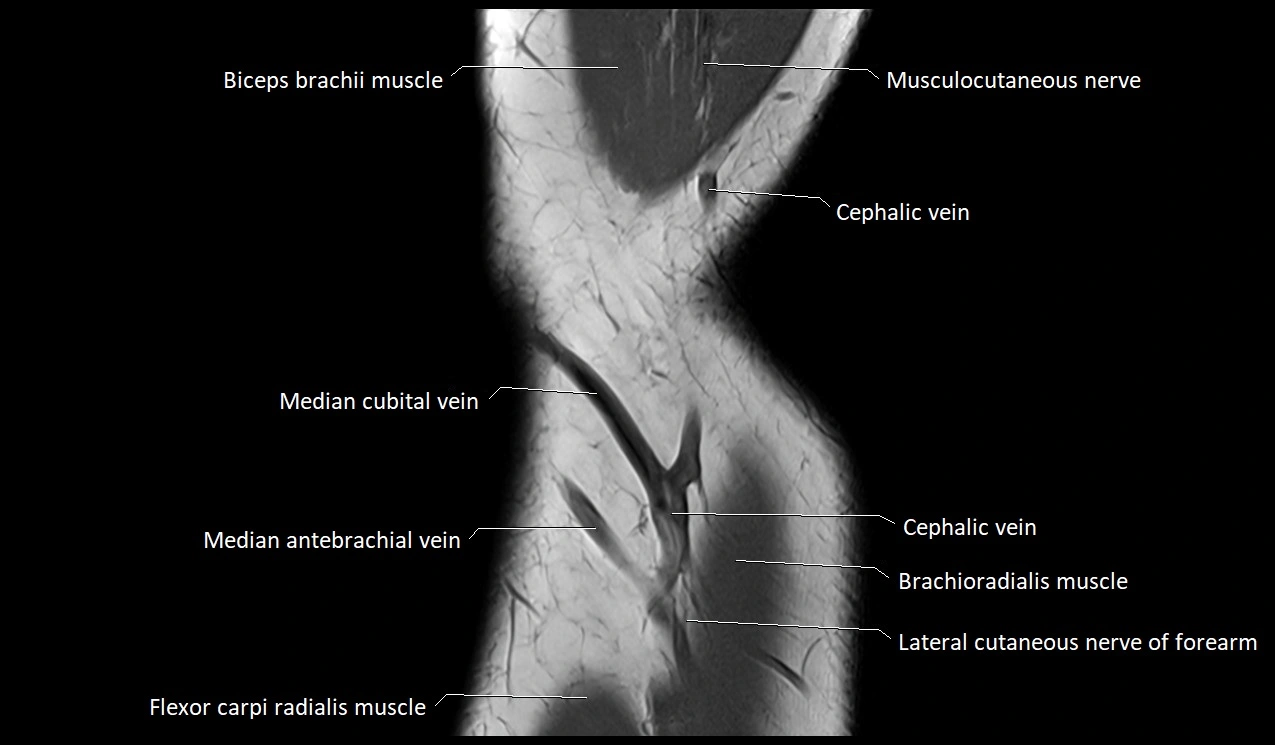

MRI image

image